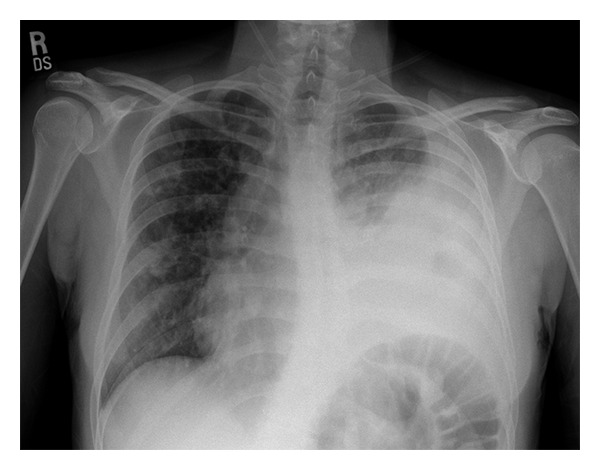

Input 3: What is seen in the X-ray and what should be done?

- Visual Med-Alpaca: Bilateral infiltrates and bilateral pleural effusion seen in a chest x-ray may indicate a respiratory infection or other respiratory conditions such as pneumonia pulmonary edema, or pleural effusion, it is important to consult a medical professional for a proper diagnosis and treatment plan.

OTHER METHODS

- VQA Medical Model: the decubitus

- Automatic Radiology Report Generation (Image-only): near complete opacification of the left hemi thorax with only a small amount of residual aerated lung in the left upper lobe .

- ChatGPT (GPT-3.5-Turbo) + Automatic Radiology Report Generation (Image-only): Opacification of the lung on an X-ray indicates that there is an abnormality in the lung tissue. In this case, the near-complete opacification of the left hemithorax with only a small amount of residual aerated lung in the left upper lobe suggests that there is likely a significant pathology present in the left lung. Possible causes of this finding include pneumonia, lung abscess, tumor or mass, or pleural effusion (fluid accumulation around the lung). It is important to determine the underlying cause of this finding as soon as possible. A follow-up diagnostic workup may include a CT scan of the chest, sputum culture, bronchoscopy, and/or a biopsy of any suspicious areas in the lung. The appropriate treatment will depend on the underlying cause, but it may include antibiotics, drainage of any fluid collections, or surgery to remove any masses or tumors. Prompt evaluation and treatment are necessary to prevent complications and improve outcomes.